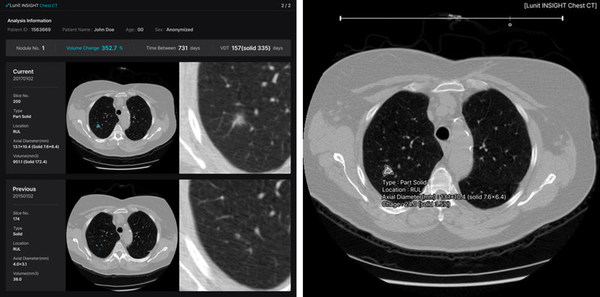

투자유치 소식에 이어 신제품 공개 소식도 전해졌다. ▲흉부 CT 데이터에 대한 AI 솔루션 '루닛 인사이트 체스트 CT(Lunit INSIGHT Chest CT)'와 ▲유방단층촬영(DBT)에 AI를 적용한 '루닛 인사이트 DBT(Lunit INSIGHT DBT)'가 그 주인공.

2개 신제품은 11월 28일부터 12월 2일까지 미국 시카고에서 열리는 북미영상의학회(RSNA)에서 첫 공개될 예정이다.

이번 RSNA에서 첫 공개될 루닛 인사이트 체스트 CT와 루닛 인사이트 DBT는 흉부 CT와 DBT 각각에 AI를 적용해 보다 빠르고 정확하게 판독해 의사 진단을 돕는 역할을 한다.

흉부 엑스레이와 유방조영술이 폐암과 유방암을 유발할 수 있는 질병을 1차적으로 발견하는 검사라면, CT와 DBT는 검출된 결절을 더 자세히 관찰해 암을 구별할 수 있는 보다 정교한 검사라 할 수 있다.

루닛 인사이트 체스트 CT는 흉부 CT 영상에서 검출된 결절의 위치, 유형, 부피, 크기 등을 3차원으로 자동 생성하는 솔루션이다. 루닛 인사이트 DBT는 AI를 활용해 병변이 의심되는 3차원 영상 이미지를 빠른 속도로 표시하는 솔루션이다. 이들 신제품은 기존 2차원 영상 진단에서 3차원으로 제품군이 확장됐다는 점에서 의미가 크다.

서범석 대표는 "이번 학회에서 내년 정식 출시를 앞둔 신제품 루닛 인사이트 체스트 CT와 루닛 인사이트 DBT를 처음 선보이게 돼 감회가 새롭다. 앞으로도 다양한 연구를 통해 학술적 신뢰도와 기술 정확도가 높은 제품을 지속 개발해 나갈 것"이라고 전했다.